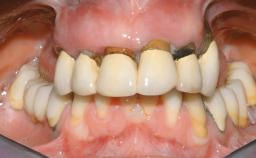

Immediate Loading of Eight Implants in the Maxilla and Six Implants in the Mandible and Final Restoration with Three-Unit and Four-Unit FDPs

Extensive scientific evidence has confirmed that immediately loaded implants with fixed full-arch provisional restorations can osseointegrate with success rates similar to conventionally or delayed loaded implants. A number of immediate-provisionalization techniques for edentulous jaws have been described. Some protocols differ when it comes to prefabricated provisional templates versus complete denture conversion; intrasurgical impressions versus direct relining; and cemented versus screw-retained provisional restorations. In this context, complete-denture conversion has been proposed for either intrasurgical impressions or direct relining. Another possibility is the utilization of a prefabricated provisional to be adapted either in the mouth (by direct relining) or in the laboratory (on a working model obtained from an intrasurgical impression).

Case Type Edentulous Maxilla

# of Teeth All

# of Implants 14